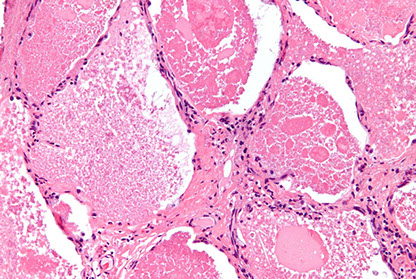

UIP

UIP/IPF - white tissue is interstitial fibrosis

UIP with patchwork distribution of fibrosis, fibroblastic foci (upper left), and honeycomb pattern (lower right)`